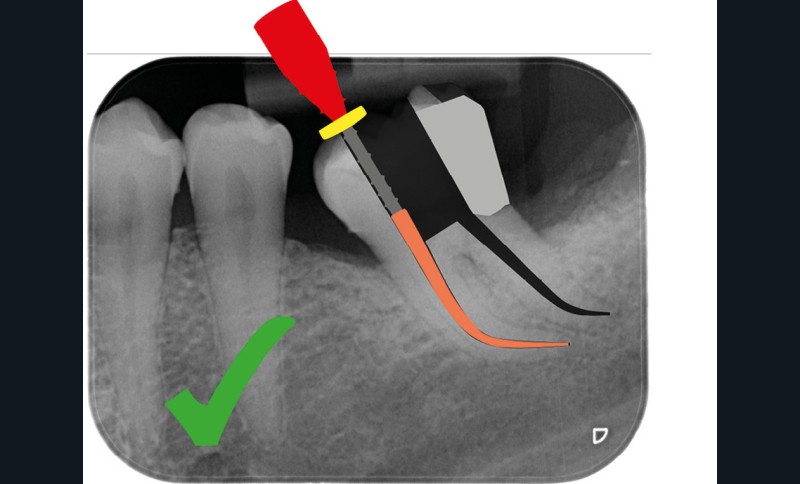

Aussi petite que possible, aussi large que nécessaire

Une cavité d’accès moderne, dictée par l’anatomie et la pathologie de la dent, optimiserait à la fois les pronostics endodontiques et biomécaniques et donc la longévité de la dent sur l’arcade (patient-centered dentistry ou dentisterie centrée sur le patient) (fig. 5).